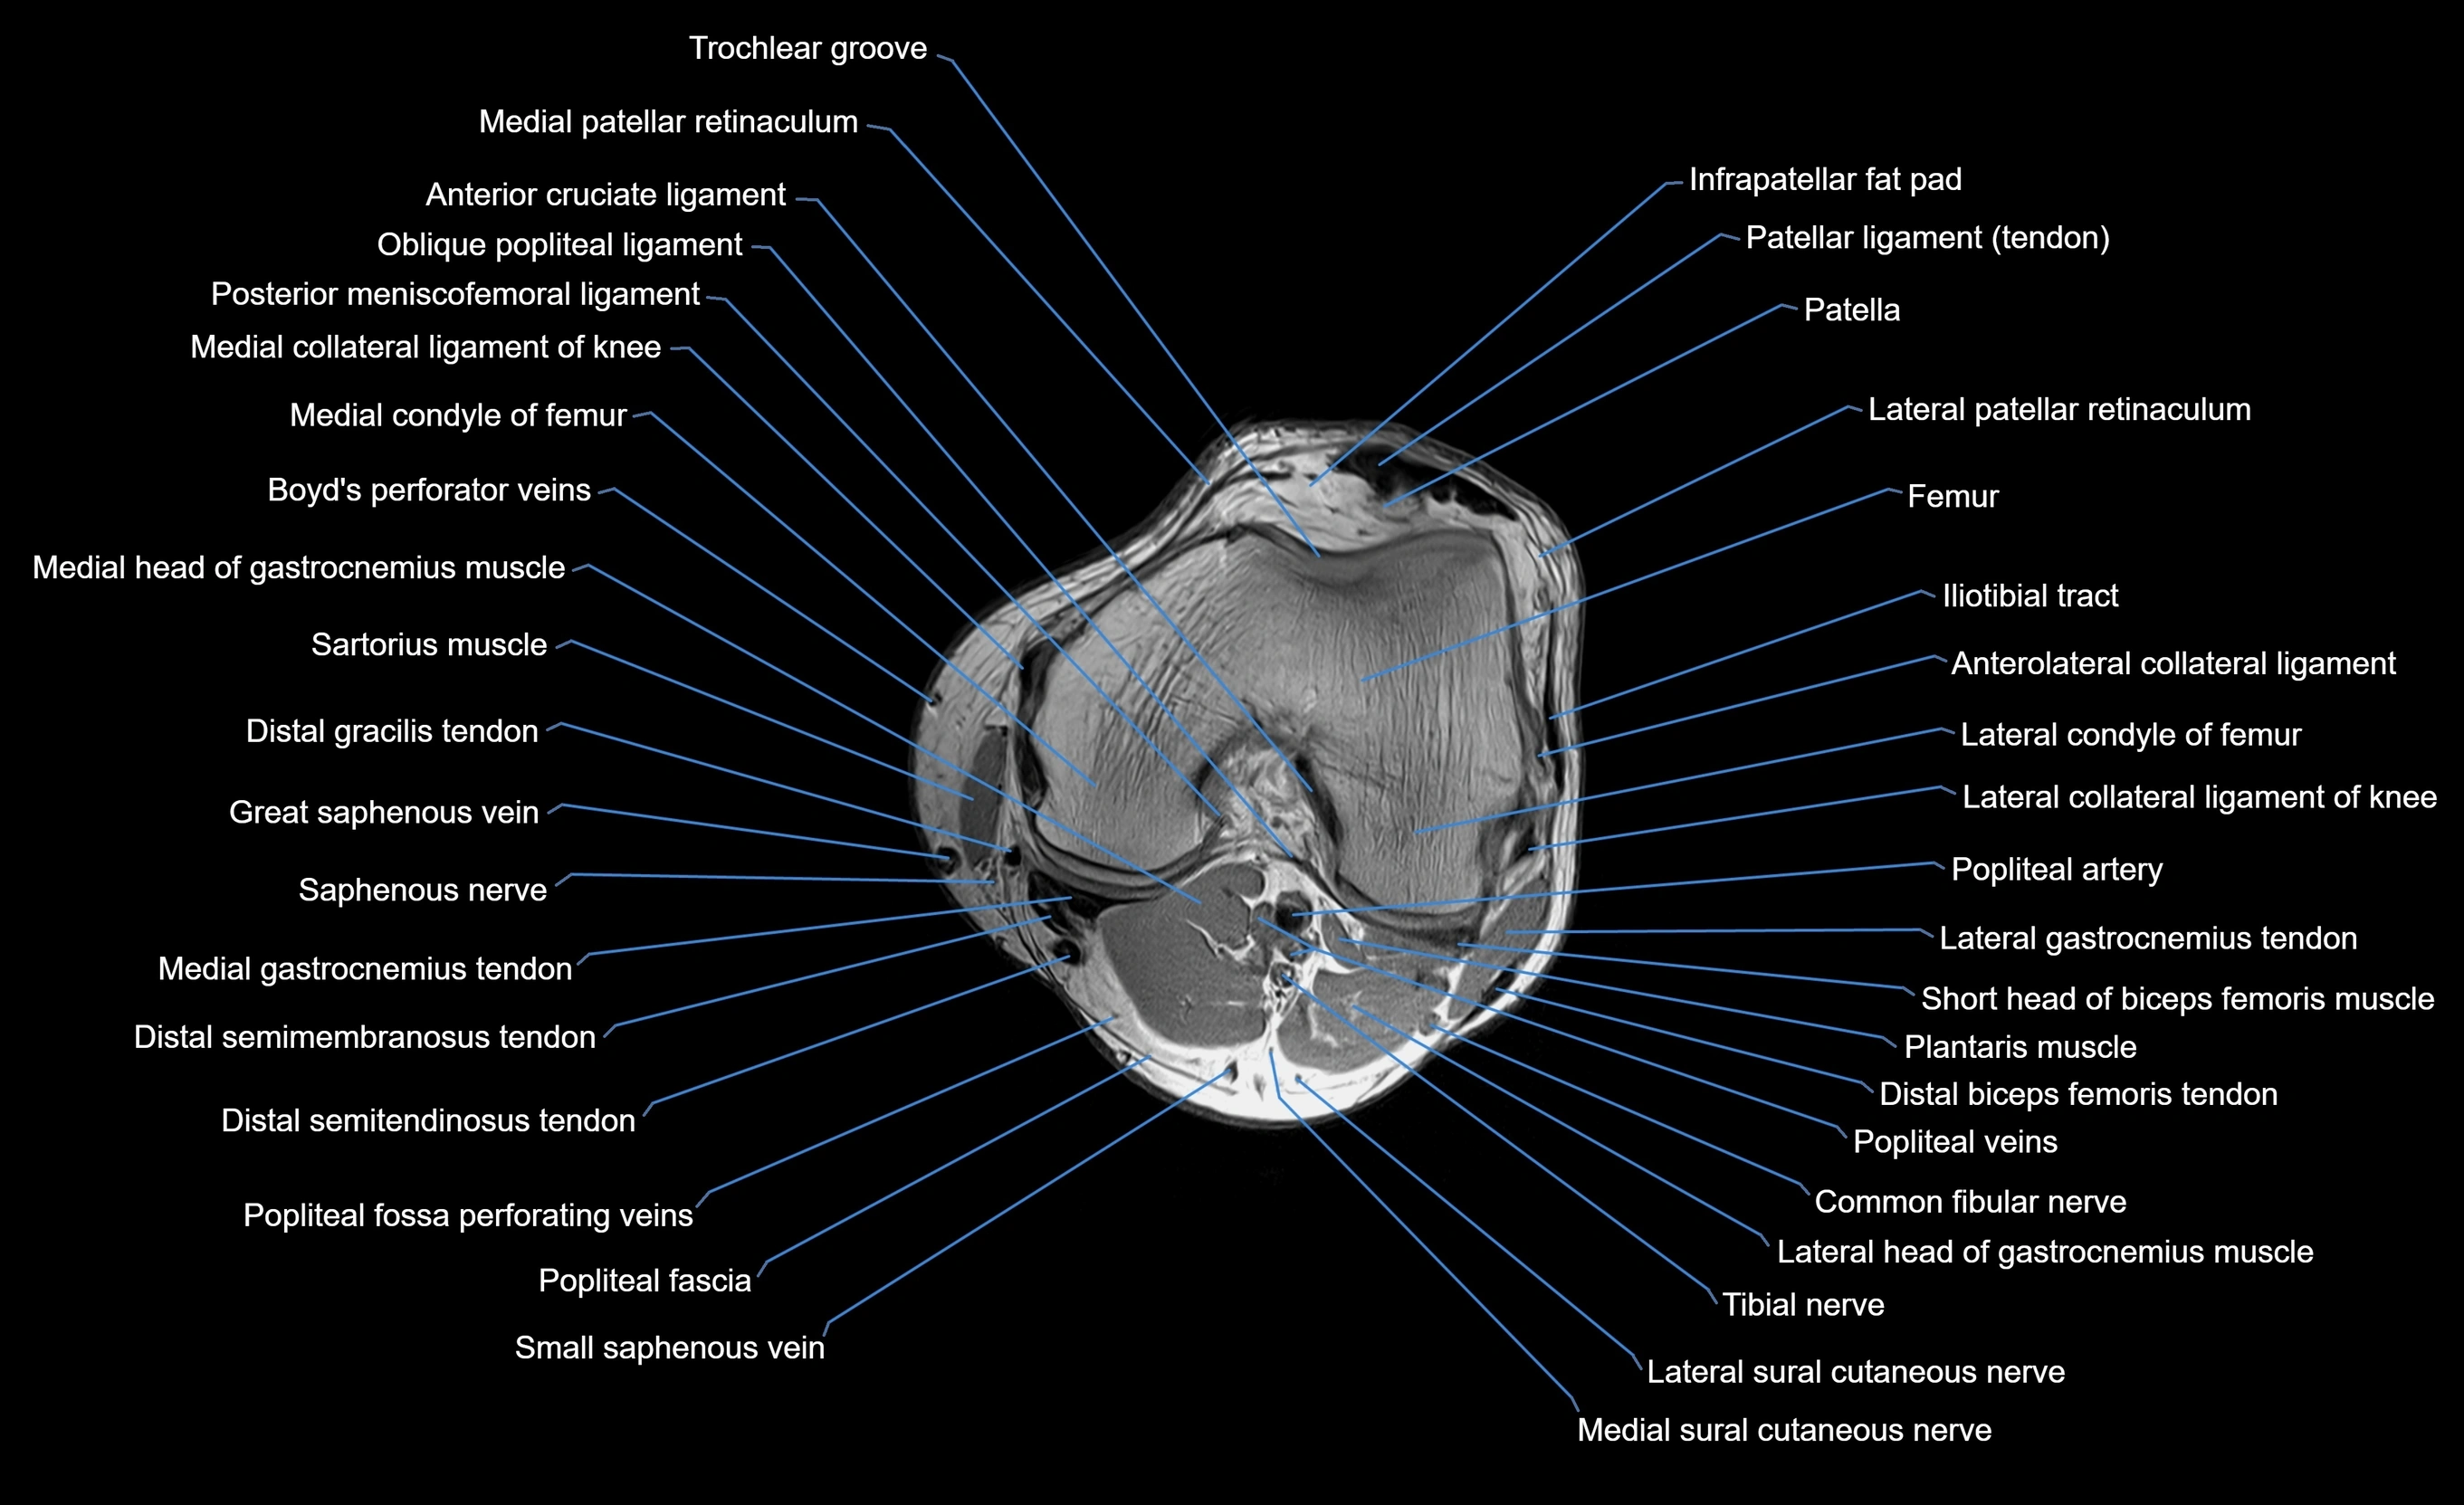

MRI image